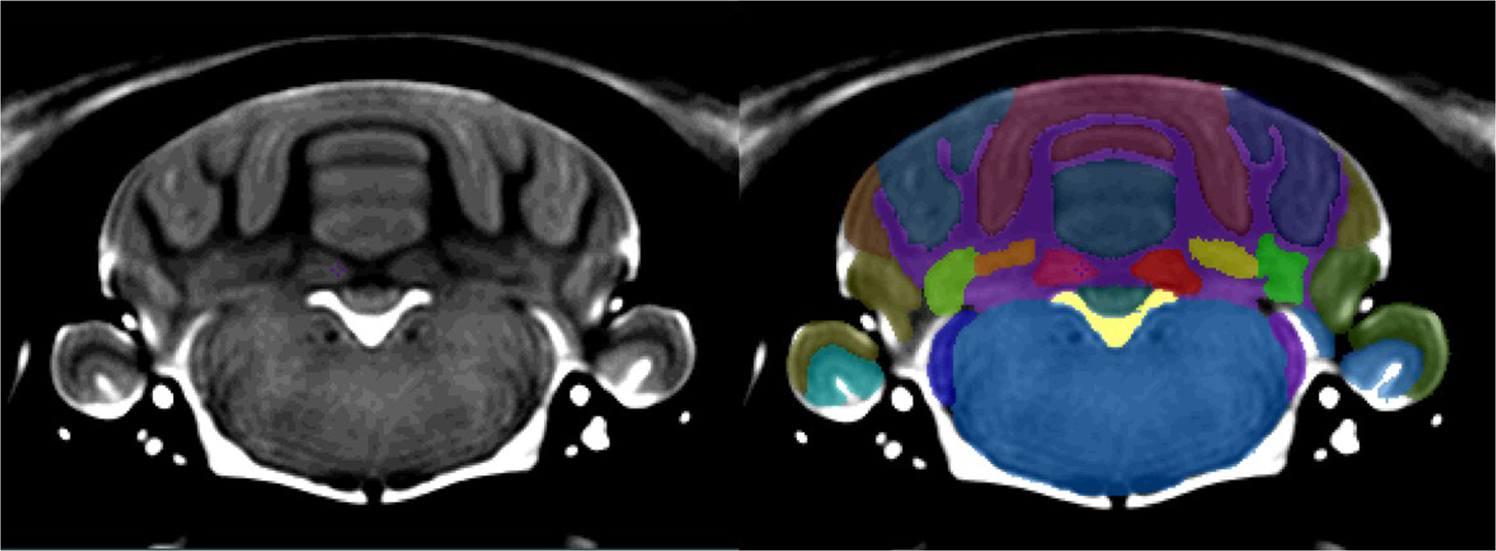

Figure 4

From: An MRI-Derived Neuroanatomical Atlas of the Fischer 344 Rat Brain

On the left is the template brain, and on the right is the template brain with the atlas file superimposed. Clear boundaries are identifiable between all of the major lobes. White matter and Arbor Vitae were indistinguishable from each other based on the resolution of the image. All the hindbrain nuclei were delineated as one structure due to poor resolution and low contrast levels in the hindbrain.